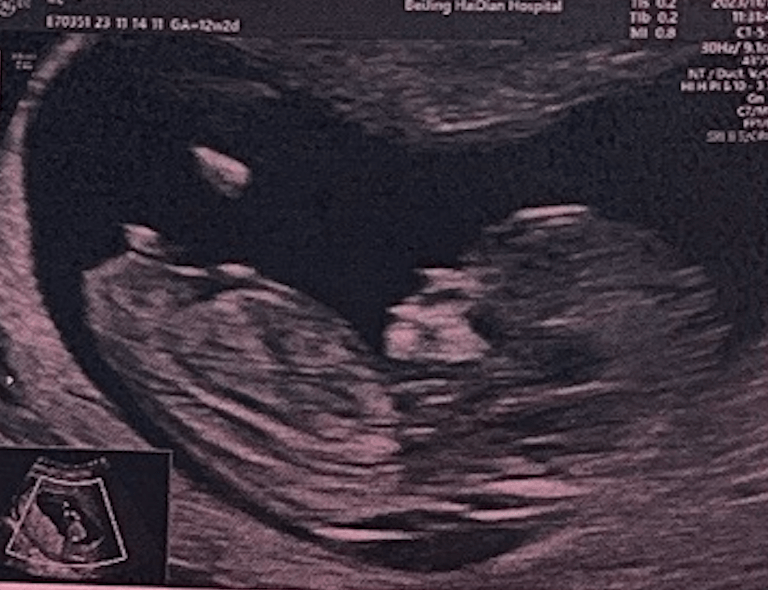

过完年我们在七七27周的时候去了一个可以做4维彩超的地方,拍了一些七七的照片,也是在这个时候我们知道了应该给她准备什么颜色的衣服。照片把一些五官都拍出来了,嘴唇和爸爸的很像。我们开始期待她的到来。

今年一个非常大的变化就是我们要成为父母了!9月份知道的这个消息,到现在还是非常的激动,当时也是迫不及待的第一时间告诉了家人,最近已经安全度过了早期的阶段,每次产检都很顺利,最近开始已经每天都有规律的胎动了,第一次感受到他这个小生命的那种心情至今还记忆犹新,明年夏天就要成为爸爸了。